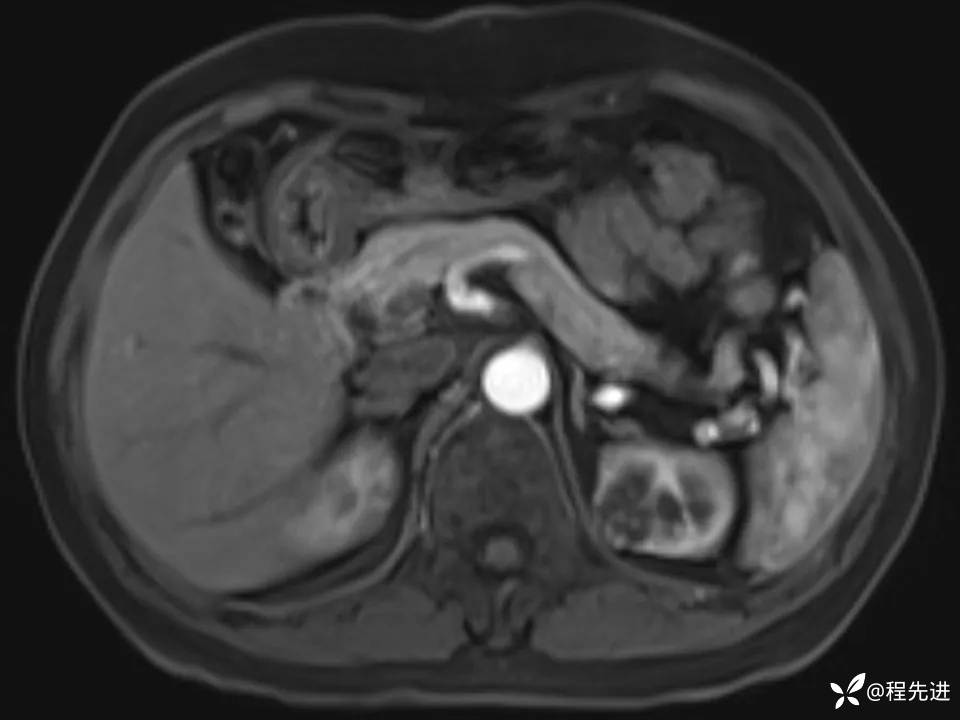

患者性别:女

患者年龄:67岁

简要病史:体检发现左肾占位,无临床症状,实验室检查无殊。

CT、MRI平扫+增强: